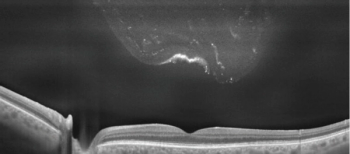

Ultra-widefield (UWF) imaging provides clinicians a much broader view of the retinal periphery. The Optos California uses multiple UWF imaging modalities, including color, autofluorescence, fluorescein angiography (FA), and indocyanine green (ICG) angiography in a 200° picture.